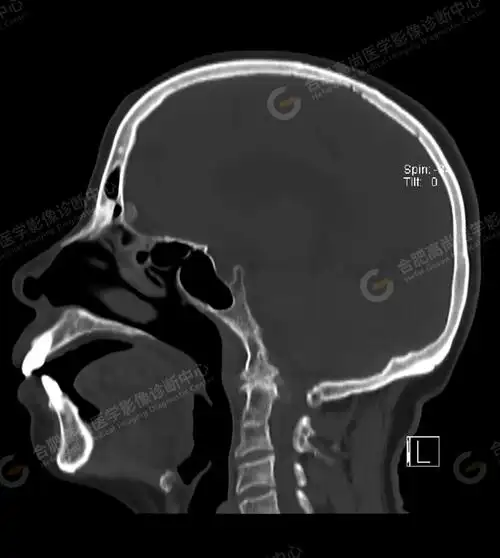

67超急性期大面积脑梗死ct平扫表现